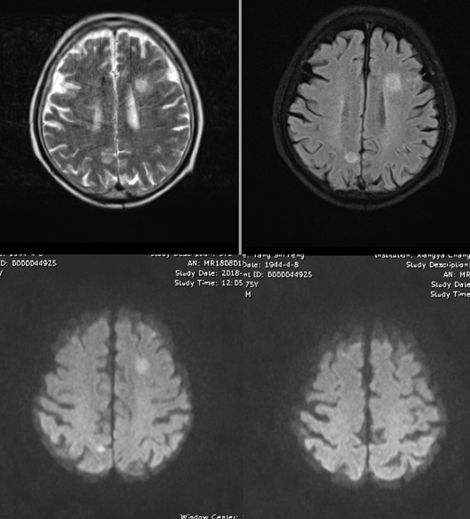

也是发烧,病程稍长。但影像上比较典型,T2、FLAIR高信号的地方,DWI也是高信号,提示脓肿。如果配上增强扫描就更理想了。病史中一是发热,二是有免疫抑制的因素,也提示感染性疾病。